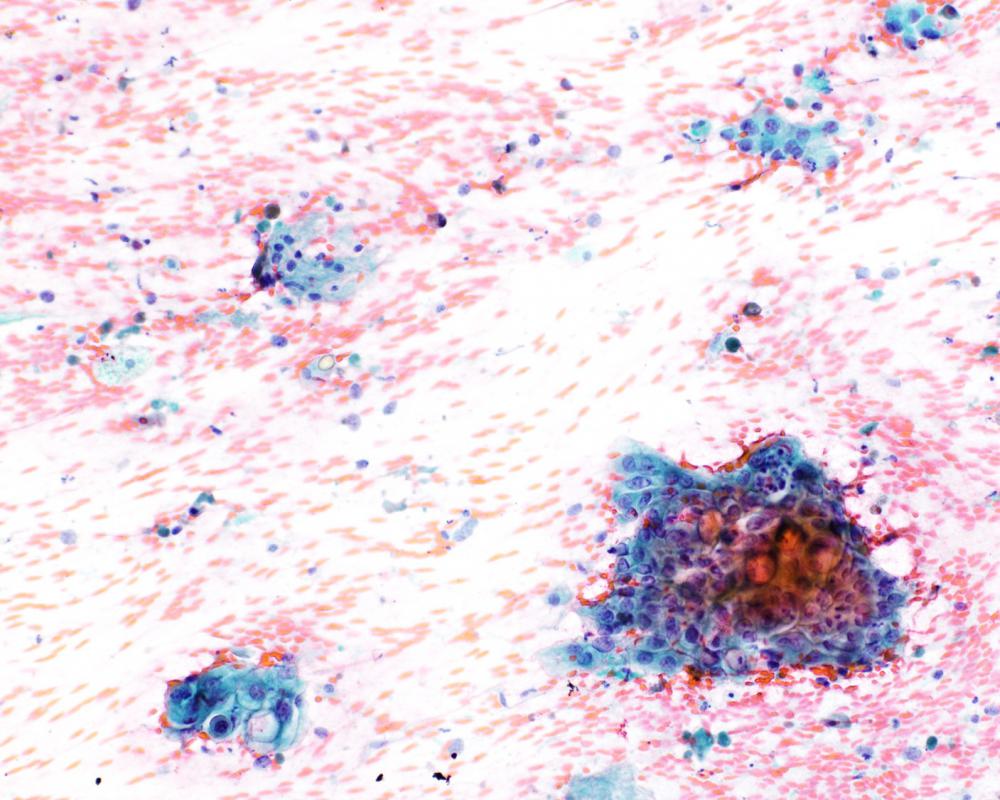

第35回日本臨床細胞学会九州連合会学会(宮崎)スライドカンファレンス症例1

種別:泌尿器

出題:長崎大学大学院医歯薬学総合研究科 病理学 林 洋子 先生

| 年齢 | 60歳代 | 性別 | 男性 |

| 採取部位 | 尿 | 採取方法 | 自然尿 |

臨床所見

既 往 歴:高血圧、高尿酸血症、PSA高値(9.17ng/ml)

現 病 歴:夜間頻尿にて受診。MRI検査にて、膀胱内腔へ突出する腫瘍が見られた。前立腺癌の尿道浸潤もしくは膀胱腫瘍が疑われた。

| 正解 | 4.膀胱原発腺癌 |

▼選択肢及び投票結果

| 1.尿細管上皮 | 10件 | (10.3%) | |

| 2.低異型度尿路上皮癌 | 4件 | (4.1%) | |

| 3.高異型度尿路上皮癌 | 4件 | (4.1%) | |

| 4.膀胱原発腺癌 | 20件 | (20.6%) | |

| 5.前立腺癌 | 59件 | (60.8%) | |

| 投票総数 | 97件 | (100%) |